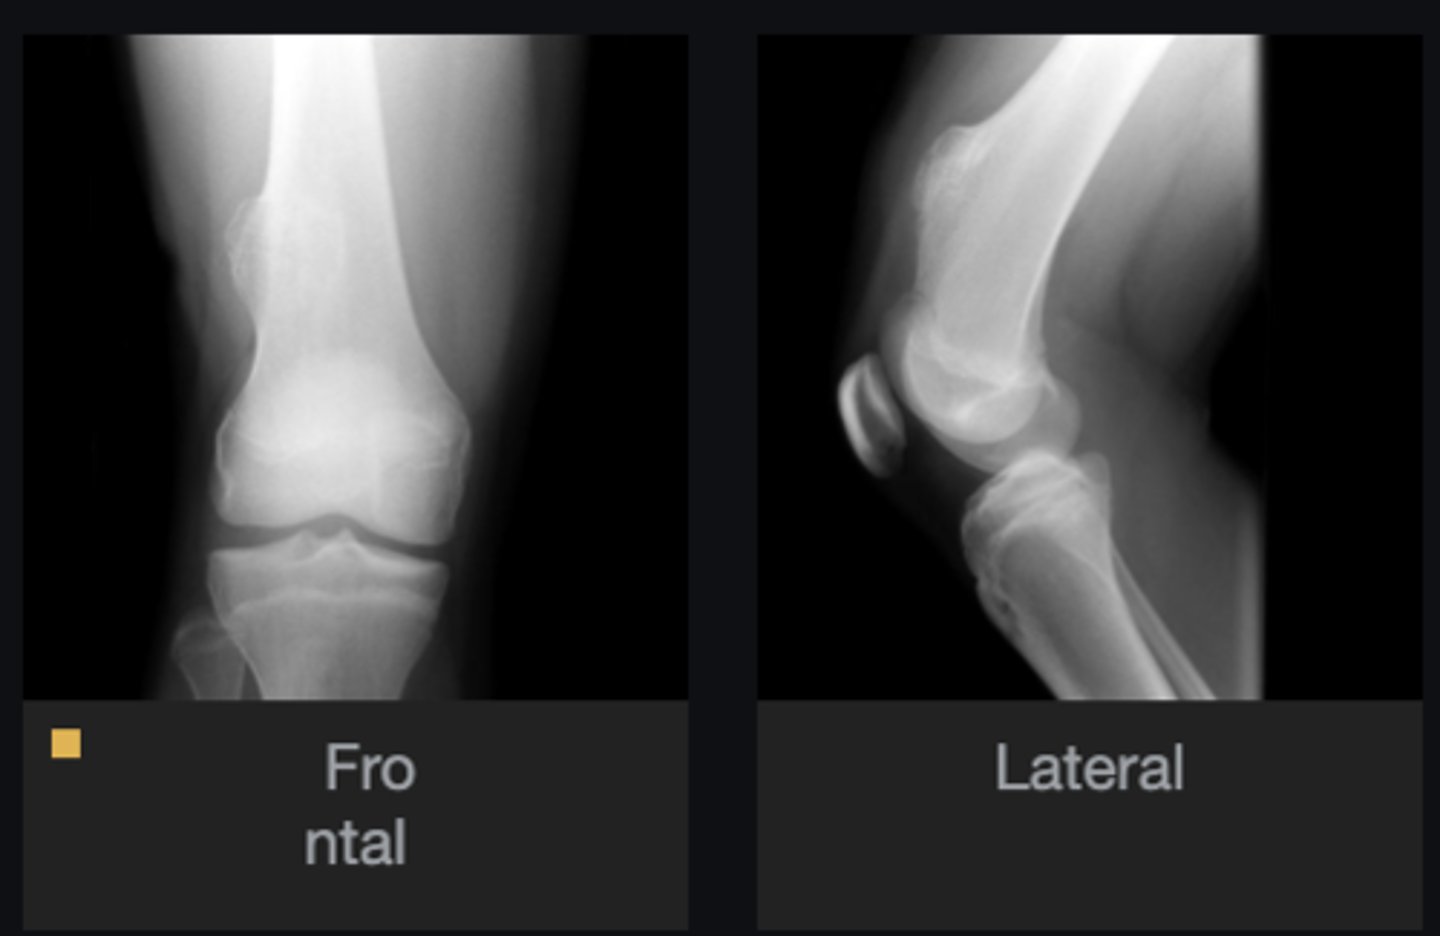

- Distal femur involved

- Elongated stalk

- Cortex and medulla are continuous

- Pointing away from joint

- Narrow base

Describe the bone lesion

Pedunculated solitary osteochondroma

Most likely diagnosis?

Refer to orthopedist

Next step?

- Fracture

- Malignant transformation (chondrosarcoma)

- Bursitis

- Neurologic injury

Concerns/complications?